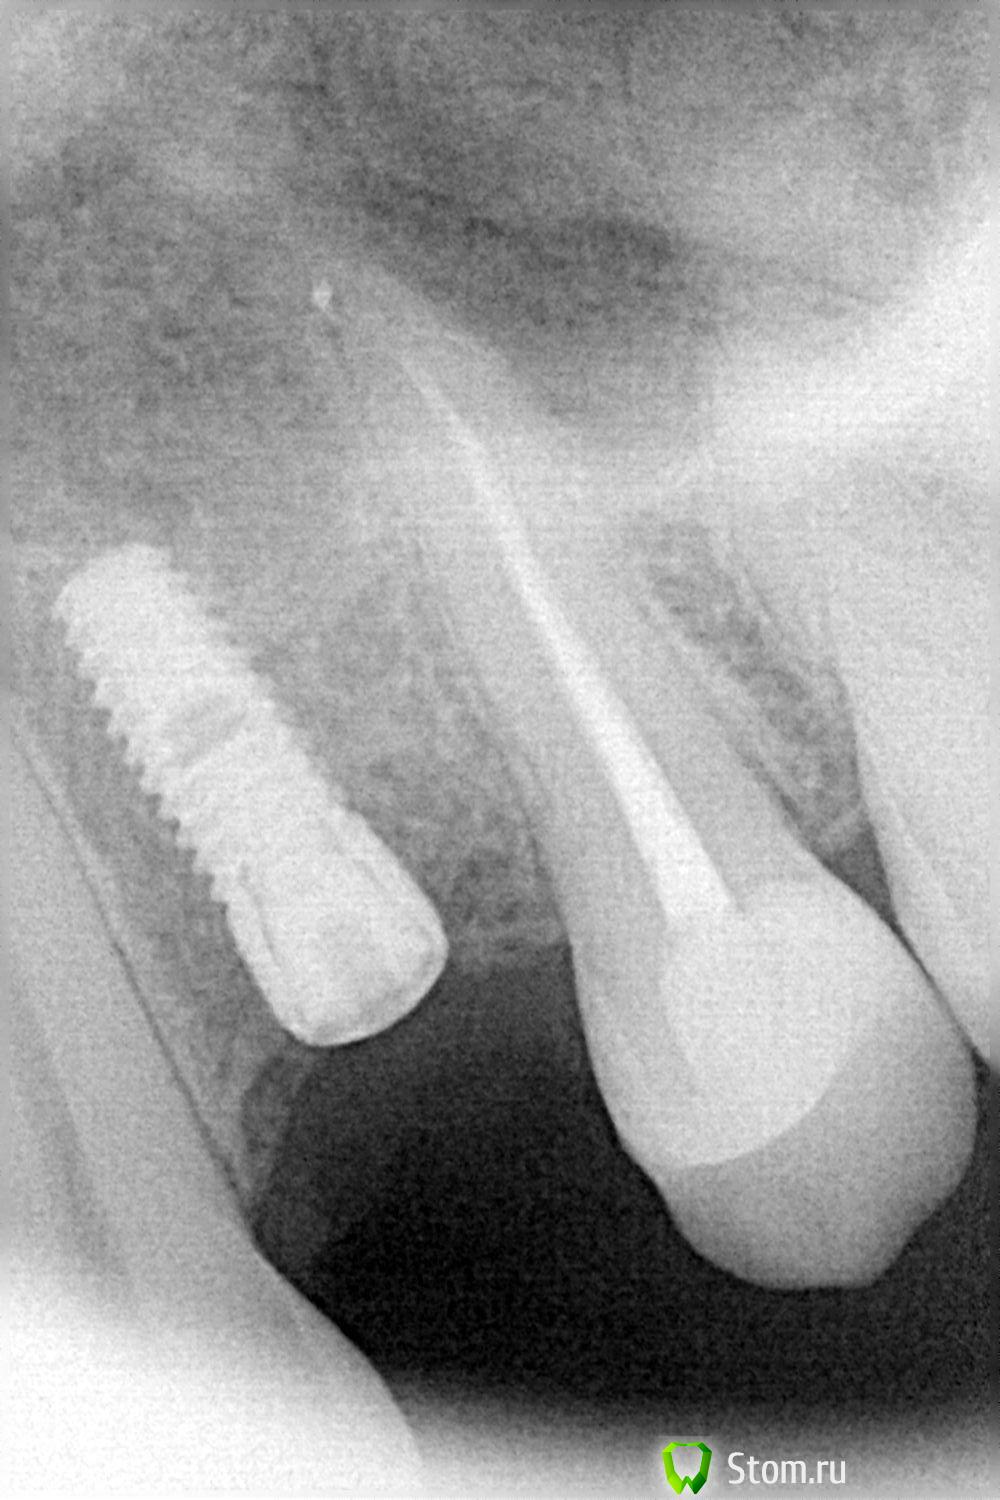

FBR Опубликовано 12 апреля, 2012 Поделиться Опубликовано 12 апреля, 2012 Добрый день коллеги! Провел пластику СДТ в области 24. Буду признателен за комментарии и советы. (извините за качество фотографий, я только начал. В последствии исправлюсь...). Ссылка на комментарий

FBR Опубликовано 12 апреля, 2012 Автор Поделиться Опубликовано 12 апреля, 2012 (изменено) Объем добавить хотелось, и прикрепленную десну Изменено 12 апреля, 2012 пользователем FBR Ссылка на комментарий